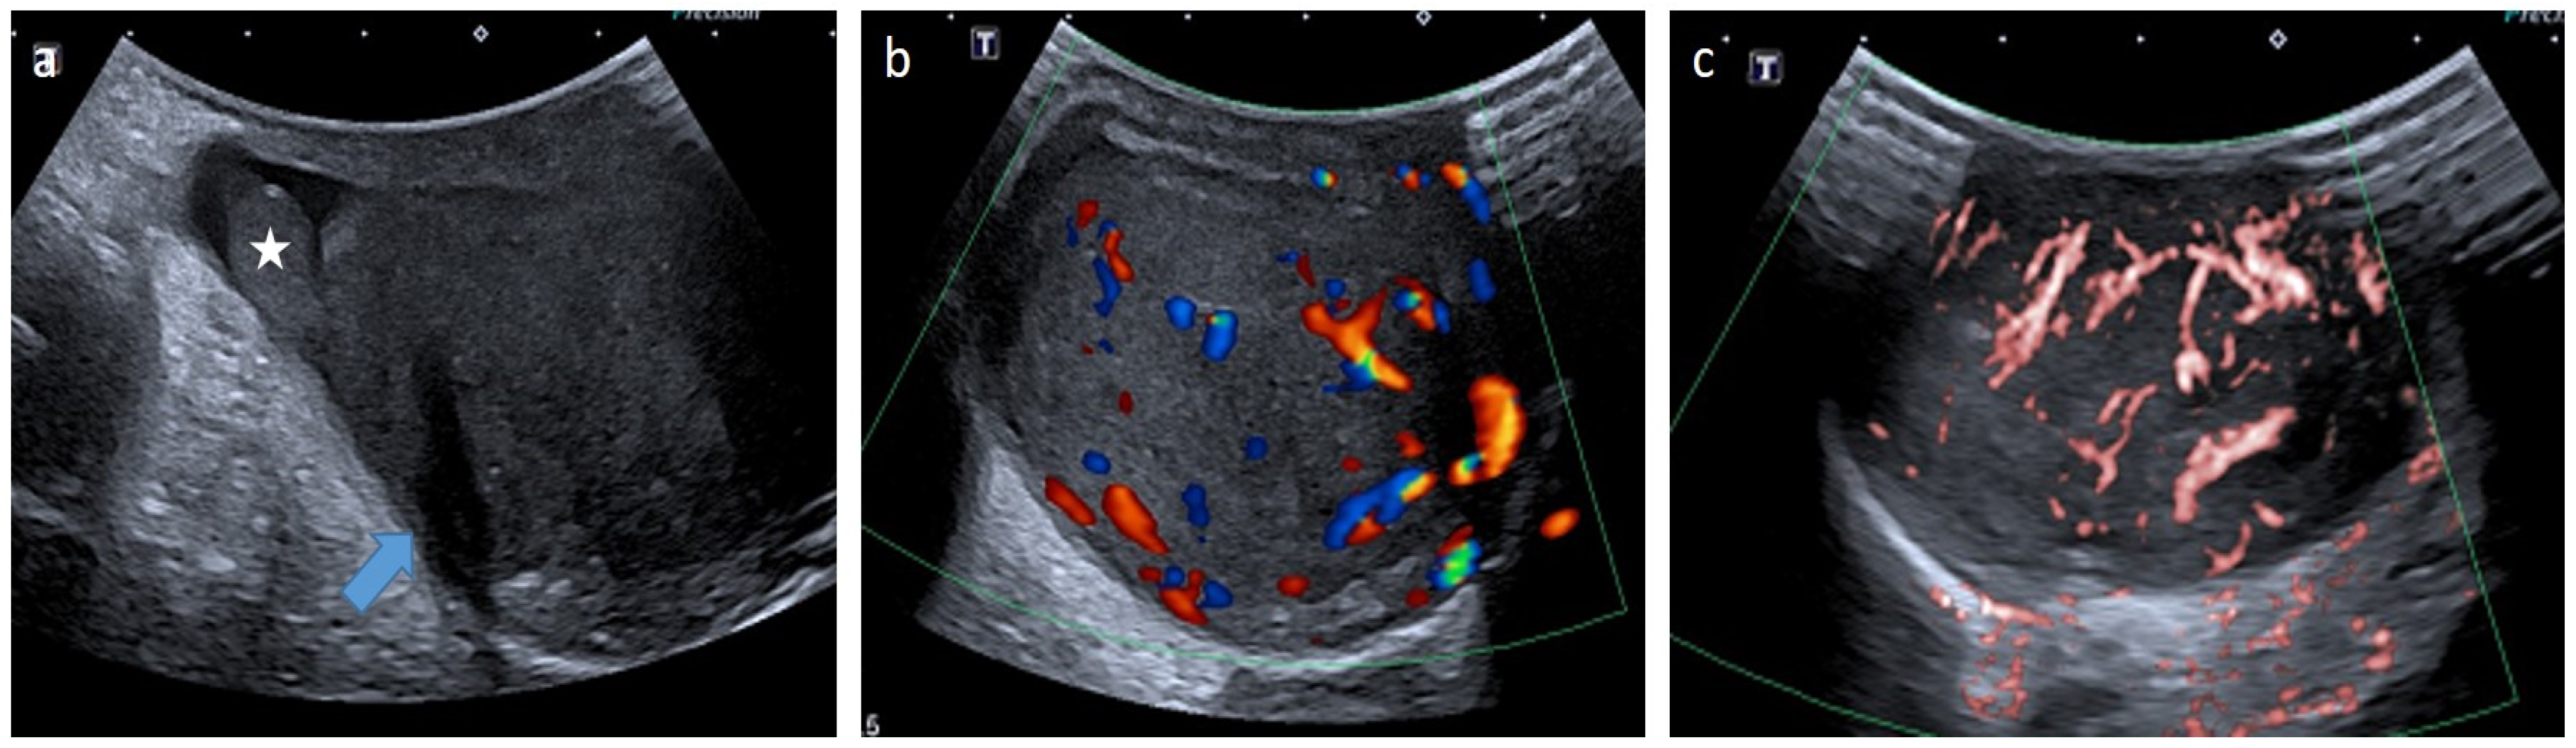

4.5.1. Leydig Cell Tumors (LCTs)

- Xu, Z.-Q.; Zhao, D.; Tian, B.-L.; Wang, Y.-B. Ultrasound characteristics of testicular Leydig cell tumors, 1. Zhonghua Nan Ke Xue 2019, 25, 346–350. [Google Scholar]

- Grand, T.; Hermann, A.-L.; Gérard, M.; Arama, E.; Ouerd, L.; Garrouche, N.; Rocher, L. Precocious puberty related to Leydig cell testicular tumor: The diagnostic imaging keys. Eur. J. Med. Res. 2022, 27, 67. [Google Scholar] [CrossRef]

- Di, M.; Qin, J. Role of contrast-enhanced ultrasound with Sonazoid in management of small testicular Leydig cell tumours: A case report with literature review. Andrologia 2021, 53, e14078. [Google Scholar] [CrossRef]

- Manganaro, L.; Vinci, V.; Pozza, C.; Saldari, M.; Gianfrilli, D.; Pofi, R.; Bernardo, S.; Cantisani, V.; Lenzi, A.; Scialpi, M.; et al. A prospective study on contrast-enhanced magnetic resonance imaging of testicular lesions: Distinctive features of Leydig cell tumours. Eur. Radiol. 2015, 25, 3586–3595. [Google Scholar] [CrossRef]

- Drudi, F.M.; Valentino, M.; Bertolotto, M.; Malpassini, F.; Maghella, F.; Cantisani, V.; Liberatore, M.; De Felice, C.; D’Ambrosio, F. CEUS Time Intensity Curves in the Differentiation Between Leydig Cell Carcinoma and Seminoma: A Multicenter Study. Ultraschall Med. Eur. J. Ultrasound 2015, 37, 201–205. [Google Scholar] [CrossRef] [PubMed]

- Maxwell, F.; Izard, V.; Ferlicot, S.; Rachas, A.; Correas, J.-M.; Benoit, G.; Bellin, M.-F.; Rocher, L. Colour Doppler and ultrasound characteristics of testicular Leydig cell tumours. Br. J. Radiol. 2016, 89, 20160089. [Google Scholar] [CrossRef] [PubMed]